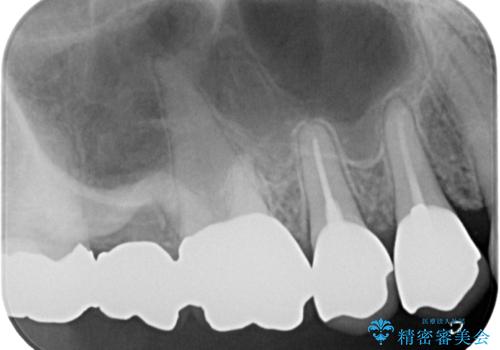

まずは根管治療を行い、痛みの消退を確認してからオールセラミッククラウンによる補綴治療を行うこととしました。

黄ばんできてしまった小臼歯部のクラウンは、根尖部に症状を認めないため、そのままオールセラミッククラウンによる補綴治療を行うこととしました。

初回の根管治療で痛みや違和感は消退したため、その後は速やかに補綴治療を行いました。